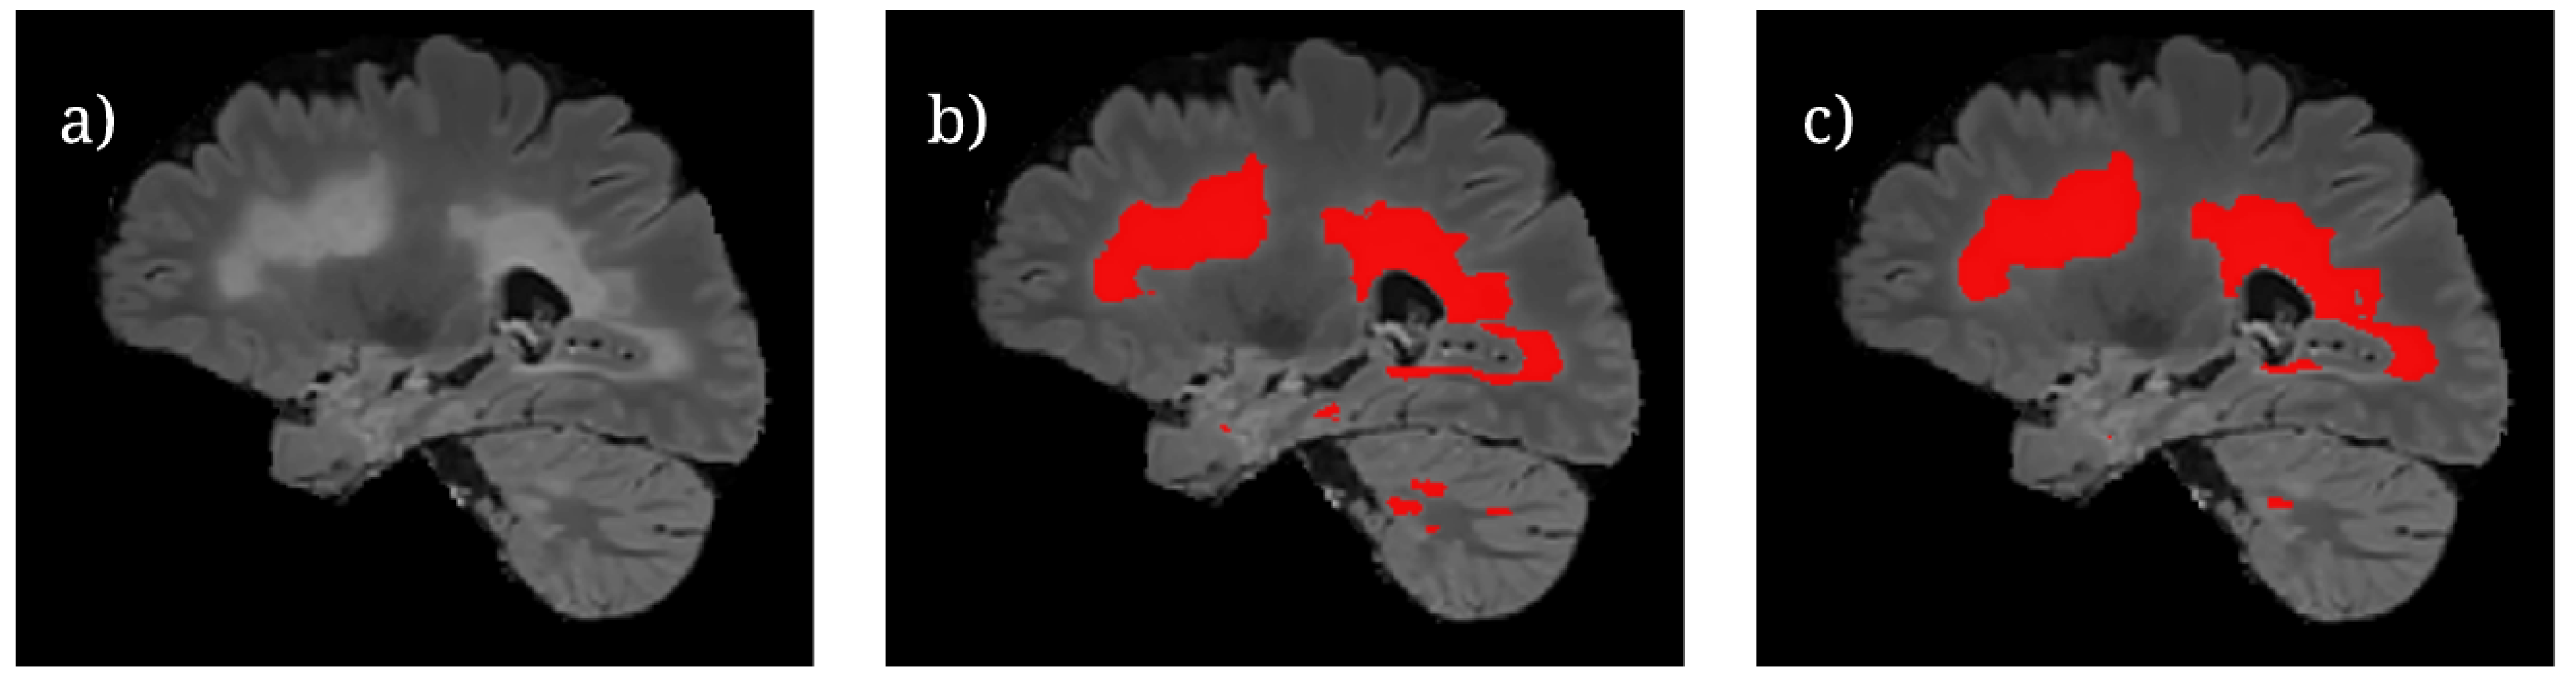

For the UMCL patients, there were three available contrasts: 2D T1, 2D T2, and 3D FLAIR. The lesions in each of these sequences are depicted differently, as shown by Figure 1. FLAIR and T2 MRIs portray lesions as hyperintensities (brighter spots) while T1 MRIs portray them as hypointensities (darker spots). The T1 sequences had been obtained with turbo inversion recovery magnitude, a repetition time (TR) of 2000 ms, an echo time (TE) of 20 ms, an inversion time (TI) of 800 ms, a flip angle (FA) of 120 ° , and a voxel size of 0.42 × 0.42 × 3.30 mm 3 . Each T2 sequence had been obtained with turbo spin echo, a TR of 6000 ms, a TE of 120 ms, an FA of 120 ° , and a voxel size of 0.57 × 0.57 × 3.00–3.30 mm 3 . Each FLAIR sequence had been obtained with a TR of 5000 ms, a TE of 392 ms, a TI of 1800 ms, an FA of 120 ° , and a voxel size of 0.47 × 0.47 × 0.80 mm 3 . Each image came in 192 × 512 × 512 volumes, with the exception of patient 11 whose image came in a volume with dimensions 176 × 512 × 512.

Figure 1. Shown are images of the same patient’s brain in the UMCL dataset [25]: (a) FLAIR MRI, (b) T2-Weighted MRI, (c) T1-Weighted MRI, and (d) consensus segmentation.